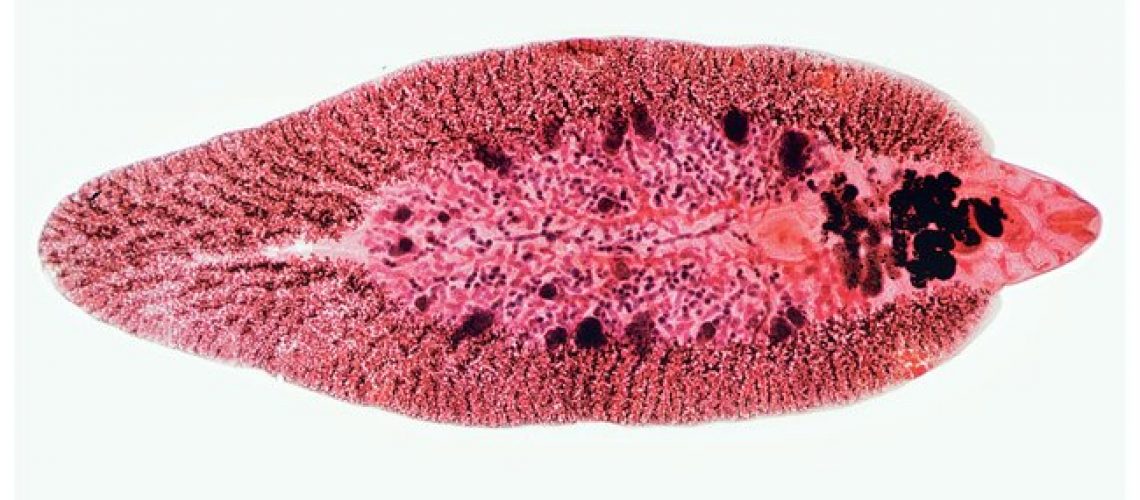

قیمت: 32٬000 تومان - دسته بندی فایل: علوم پزشکیپاورپوینت فاسیولاهپاتیکا

فروش ویژه پاور پوینت حرفه ای فاسیولاهپاتیکا با تخفیف استثنایی فقط 55 هزار تومان تعداد اسلاید: 21 اسلاید